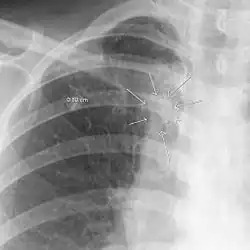

| The arrows denote an ill-defined nodular opacity in medial aspect of right upper lobe with ill-defined rim of lucency surrounding it | |

| Differential diagnosis | Aspergilloma |

In radiology, the air crescent sign (also called the Monad sign[1]) is a finding on chest radiograph and computed tomography that is crescenteric and radiolucent, due to a lung cavity that is filled with air and has a round radiopaque mass.[2] Classically, it is due to an aspergilloma, a form of aspergillosis, that occurs when the fungus Aspergillus grows in a cavity in the lung.[3]